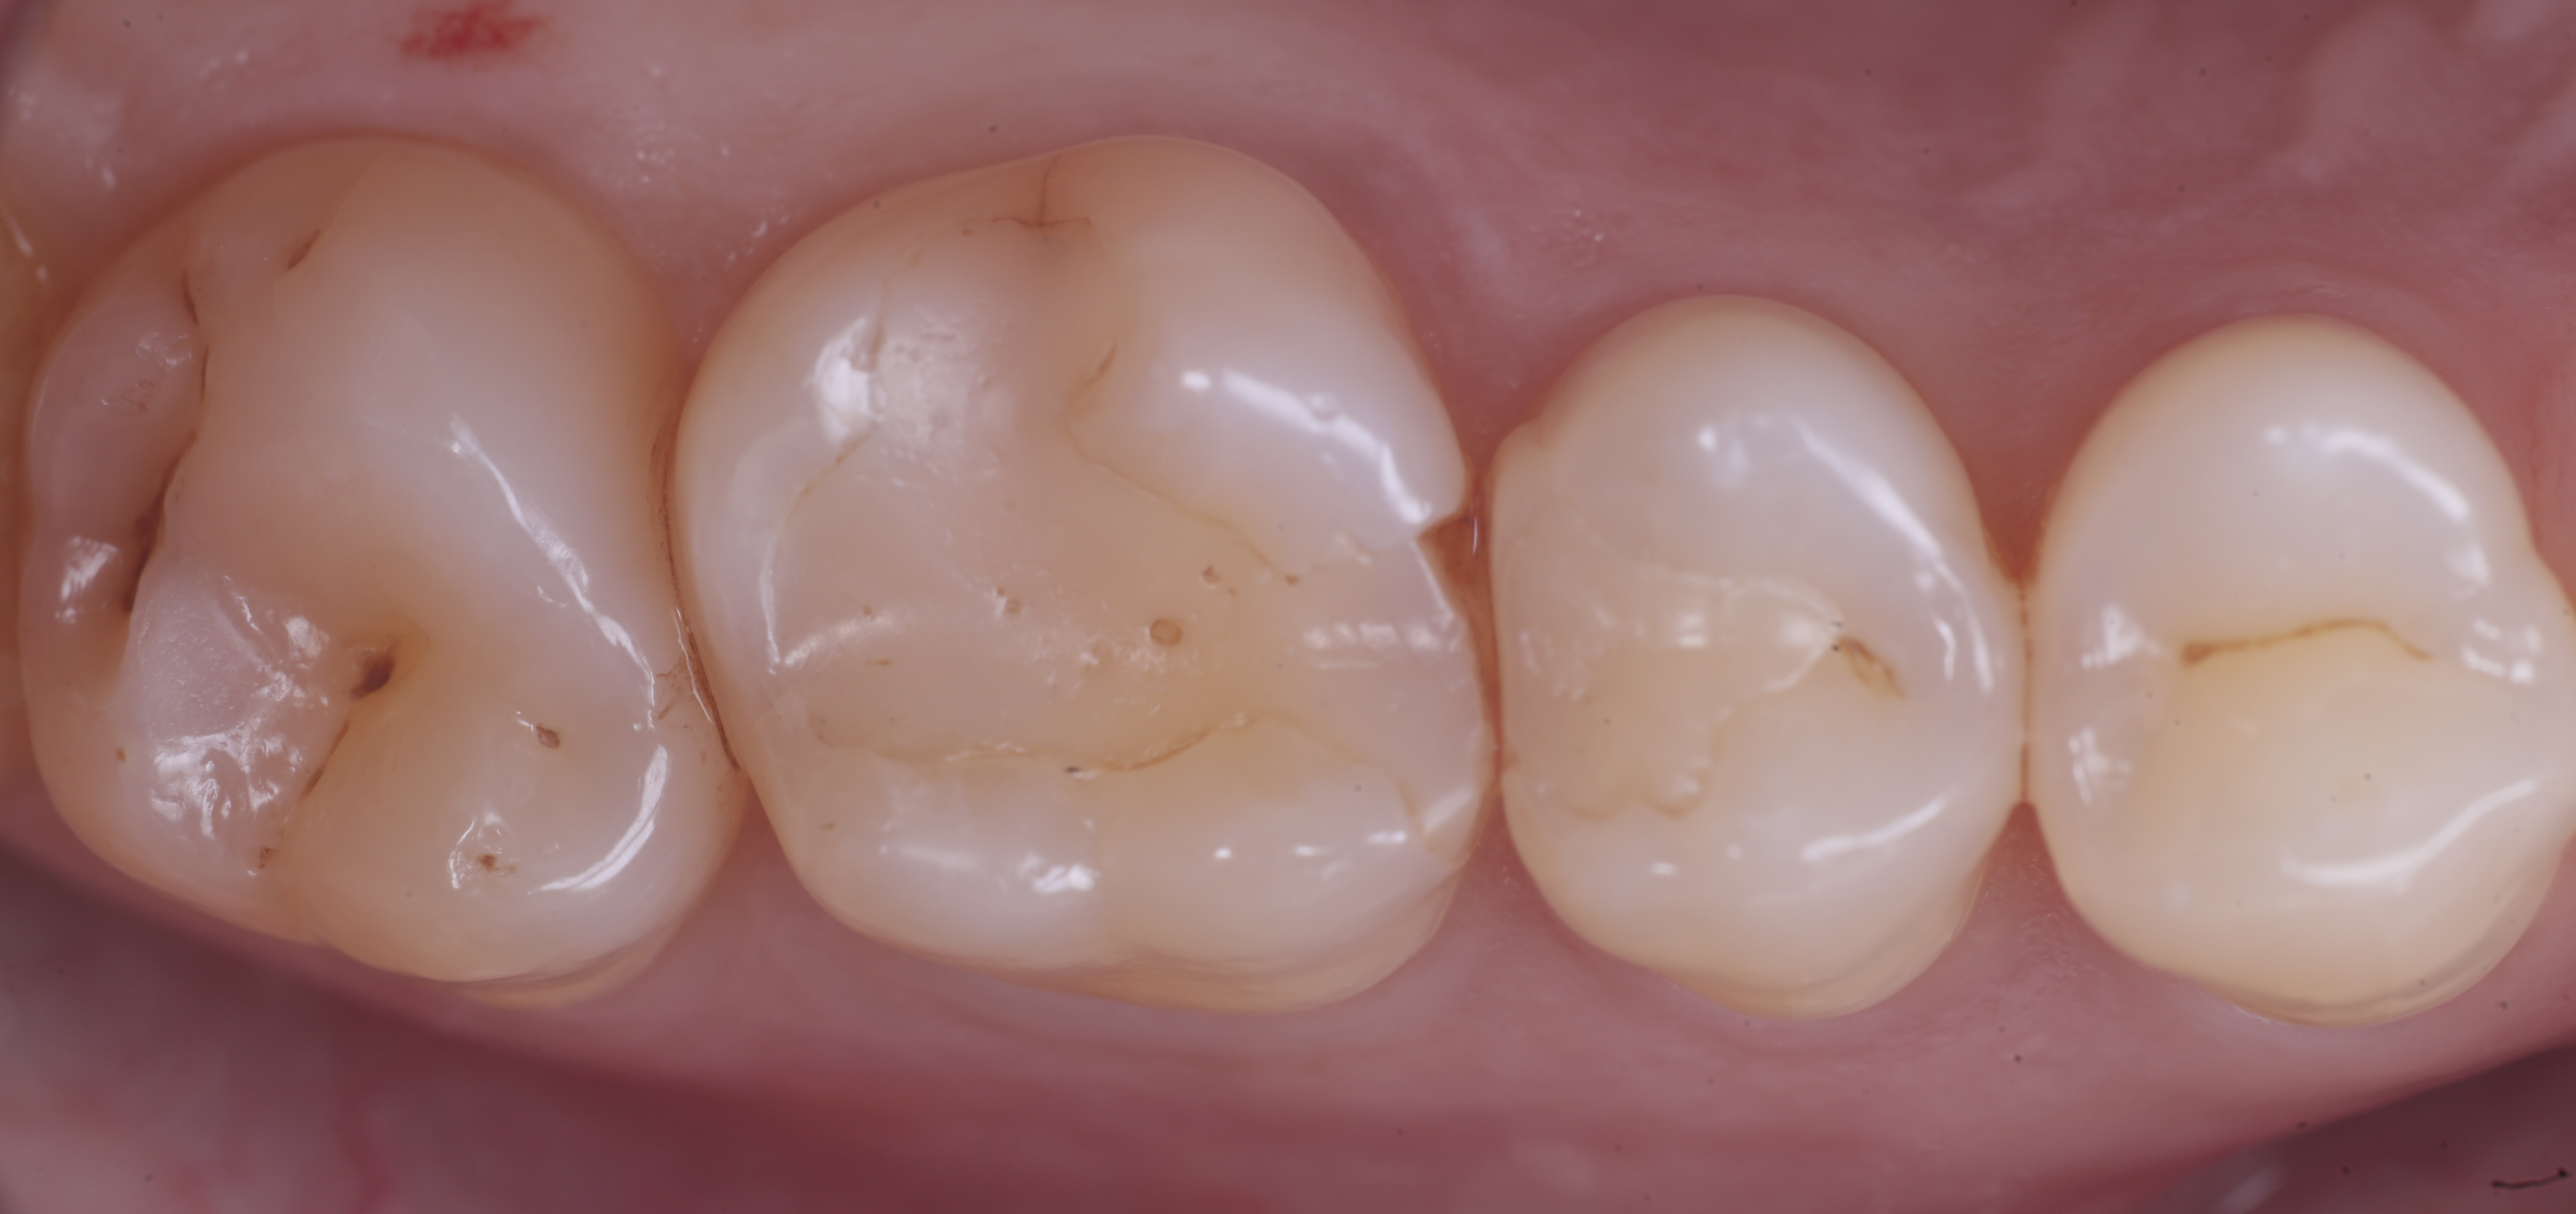

foto 11 Restauri ultimati sotto controllo occlusale

Trasformate le cavita da II classi a I classi si procede con la classica modellazione cuspide per cuspide, sfruttando le caratteristiche meccaniche e anche estetiche dei materiali compositi bulk.